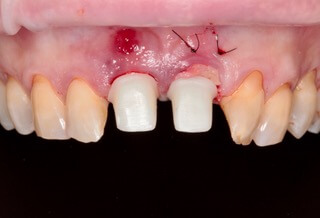

Do známeho českého časopisu Implants sme prispeli kapitolou, v ktorej Dr. Michal Repaši popisoval klinický prípad navigovanej chirurgie z praxe. Išlo o 45 ročnú pacientku, ktorá sa obrátila na našu kliniku s bolesťou v oblasti horných stredných rezákov. Pri dôkladnom vyšetrení a CT diagnostike bola v oblasti zuba č. 11 zistená vertikálna fraktúra koreňa. V oblasti zuba č. 21 palatinálne bol prítomný hlboký kaz koreňa.

Jediným riešením bola extrakcia obidvoch zubov. Najväčšou obavou zo strany pacientky bola strata obidvoch predných zubov a následného fungovania bez nich pri práci s ľuďmi.

Ukážka - navigovaná chirurgia z praxe